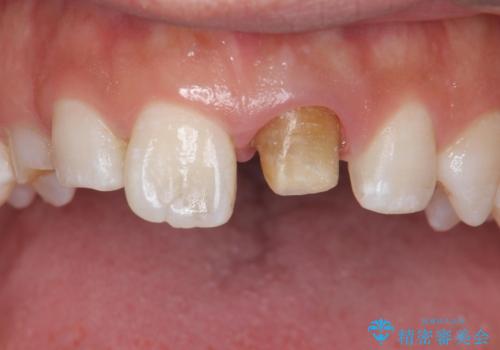

根管治療からのやり直しをした後、ジルコニアクラウンで色調の改善をしていきます。

- 左上1:根管治療(リトリートメント・前歯)/99,000円 ファイバーコア/22,000円 仮歯/11,000円 ジルコニアクラウン(スタンダード)/121,000円 合計253,000円費用は治療当時の料金となります

被せ物を装着する際は、歯の中(根管)から綺麗にすることも重要となります。